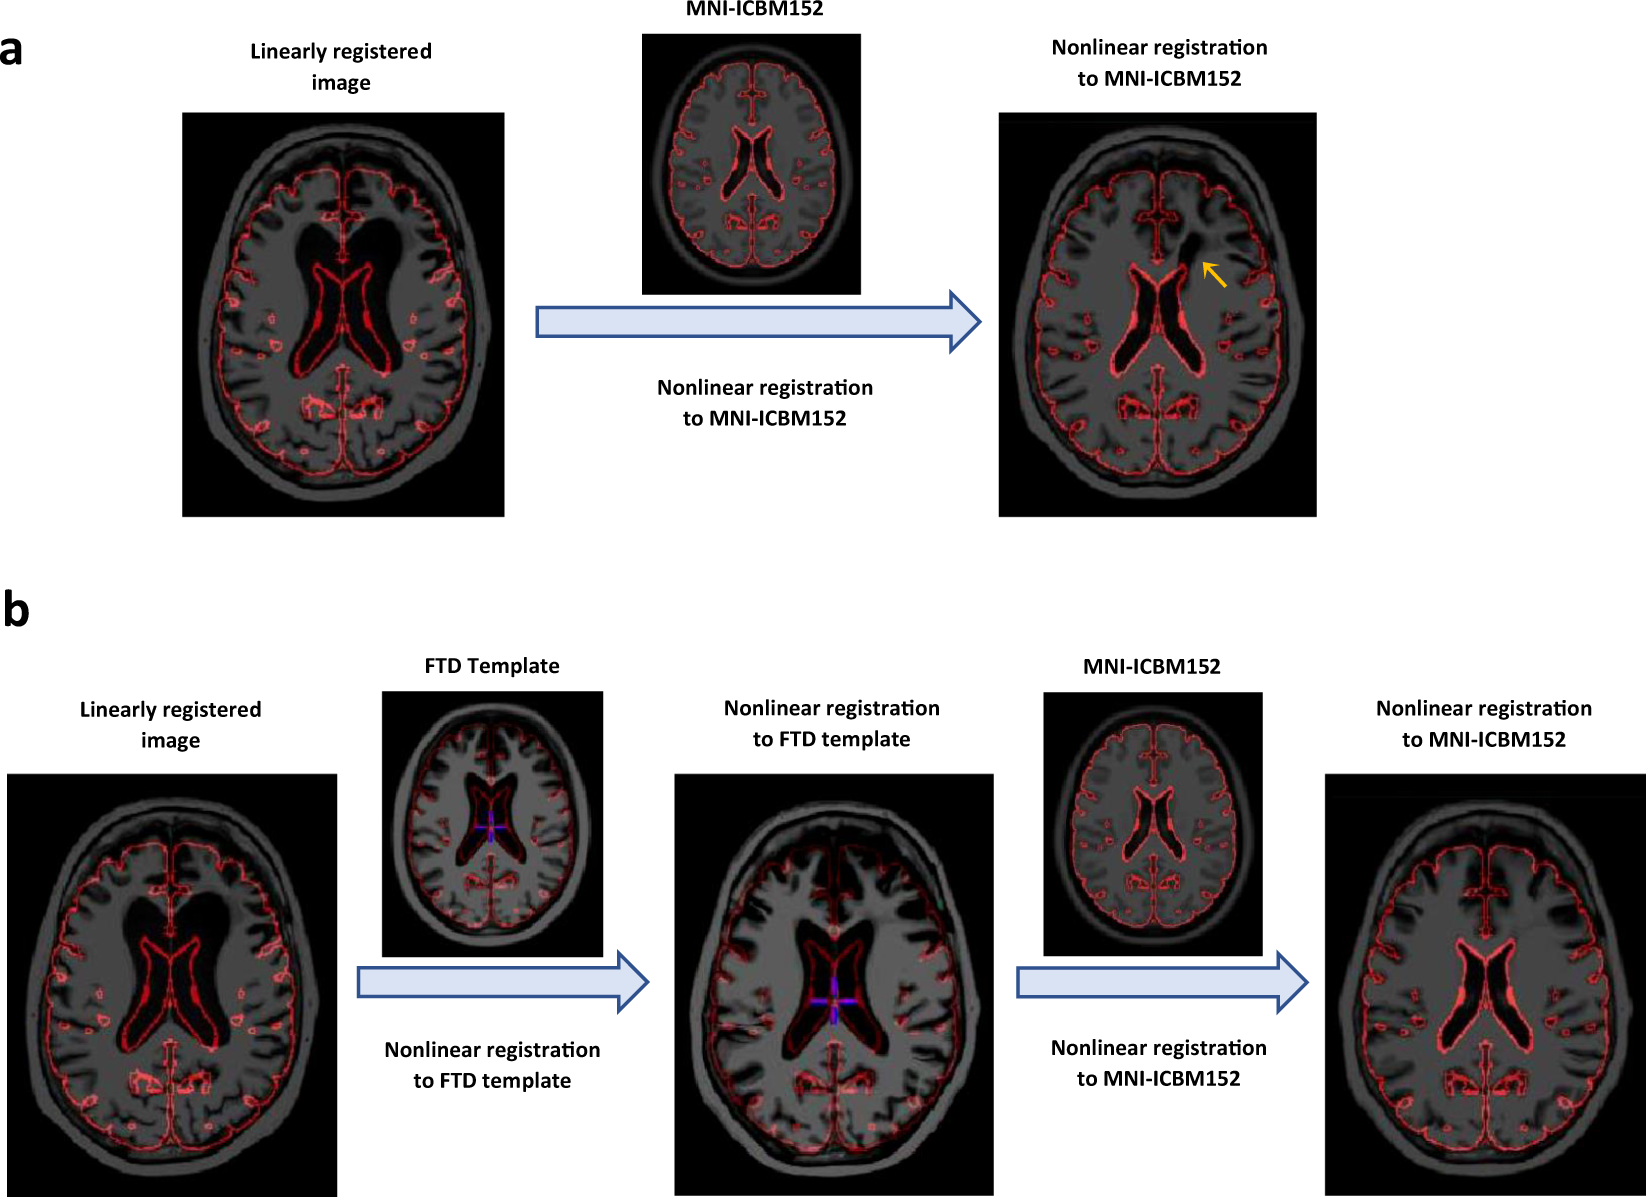

An example of T1-weighted scan of an individual with frontotemporal dementia (FTD) that was nonlinearly registered to MNI-ICBM152 average template directly (a) and using a disease appropriate template as an intermediate registration target (b). The red contour shows the outline of MNI-ICBM152 template, and can be used to assess registration accuracy. The orange arrow shows the areas of gross registration failure.